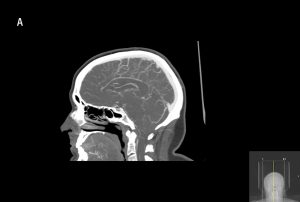

Riktade utredningar och behandlingar genomförs för de tillstånd som bedöms kunna föreligga. Endotrakeal intubation övervägs hos djupt medvetandesänkta patienter för att säkra luftvägen och skydda mot aspiration. Den traditionella intubationsgränsen är GCS ≤8, men intubation kan avstås vid snabbt reversibla tillstånd eller vara indicerad vid GCS >8, till exempel vid tillstånd med förväntad försämring i medvetandegrad [34]. Förutom patientnära prov tas prov på leukocyter och trombocyter, koagulationsstatus, CRP, leverenzymer [34] och totalt CK/myoglobin om rabdomyolys kan föreligga. Urintoxikologiskt prov ger ofta falskt positiva och negativa svar som vilseleder den diagnostiska processen och rekommenderas därför inte [75-77]. Urinretention upptäcks med ultraljud. Vid misstänkt strukturell orsak beställs DT hjärna. Vid misstänkt dissektion, basilarisocklusion eller venös sinustrombos beställs även DT-angiografi/-venografi av halskärl och intrakraniella kärl. Vid misstänkt status epilepticus beställs akut-EEG för att utesluta fortsatt subklinisk anfallsaktivitet [78].